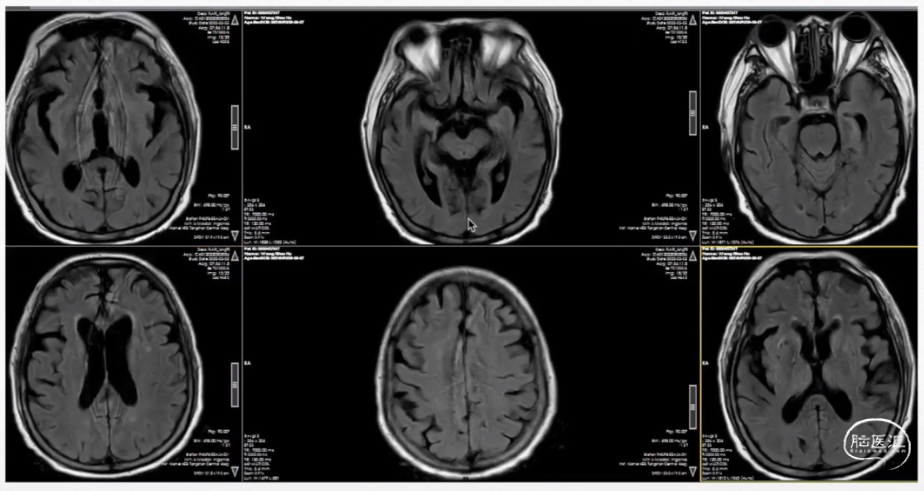

诊断

需具备以下三个核心要素:

①认知功能障碍:

主诉或由知情者报告有存在认知功能损害,并且客观检查也有认知功能损害的证据,和/或客观检查证实认知功能较以前减退。

②血管因素:

包括脑血管病的危险因素、卒中病史、神经系统局灶性体征及影像学提供的脑血管病的证据,以上各项不一定同时具备。

③认知功能障碍与血管因素存在因果关系:

通过询问病史、体格检查、实验室和影像学检查明确患者的认知功能障碍与血管因素有因果关系,并除外其他导致认知功能障碍的原因。

![]()